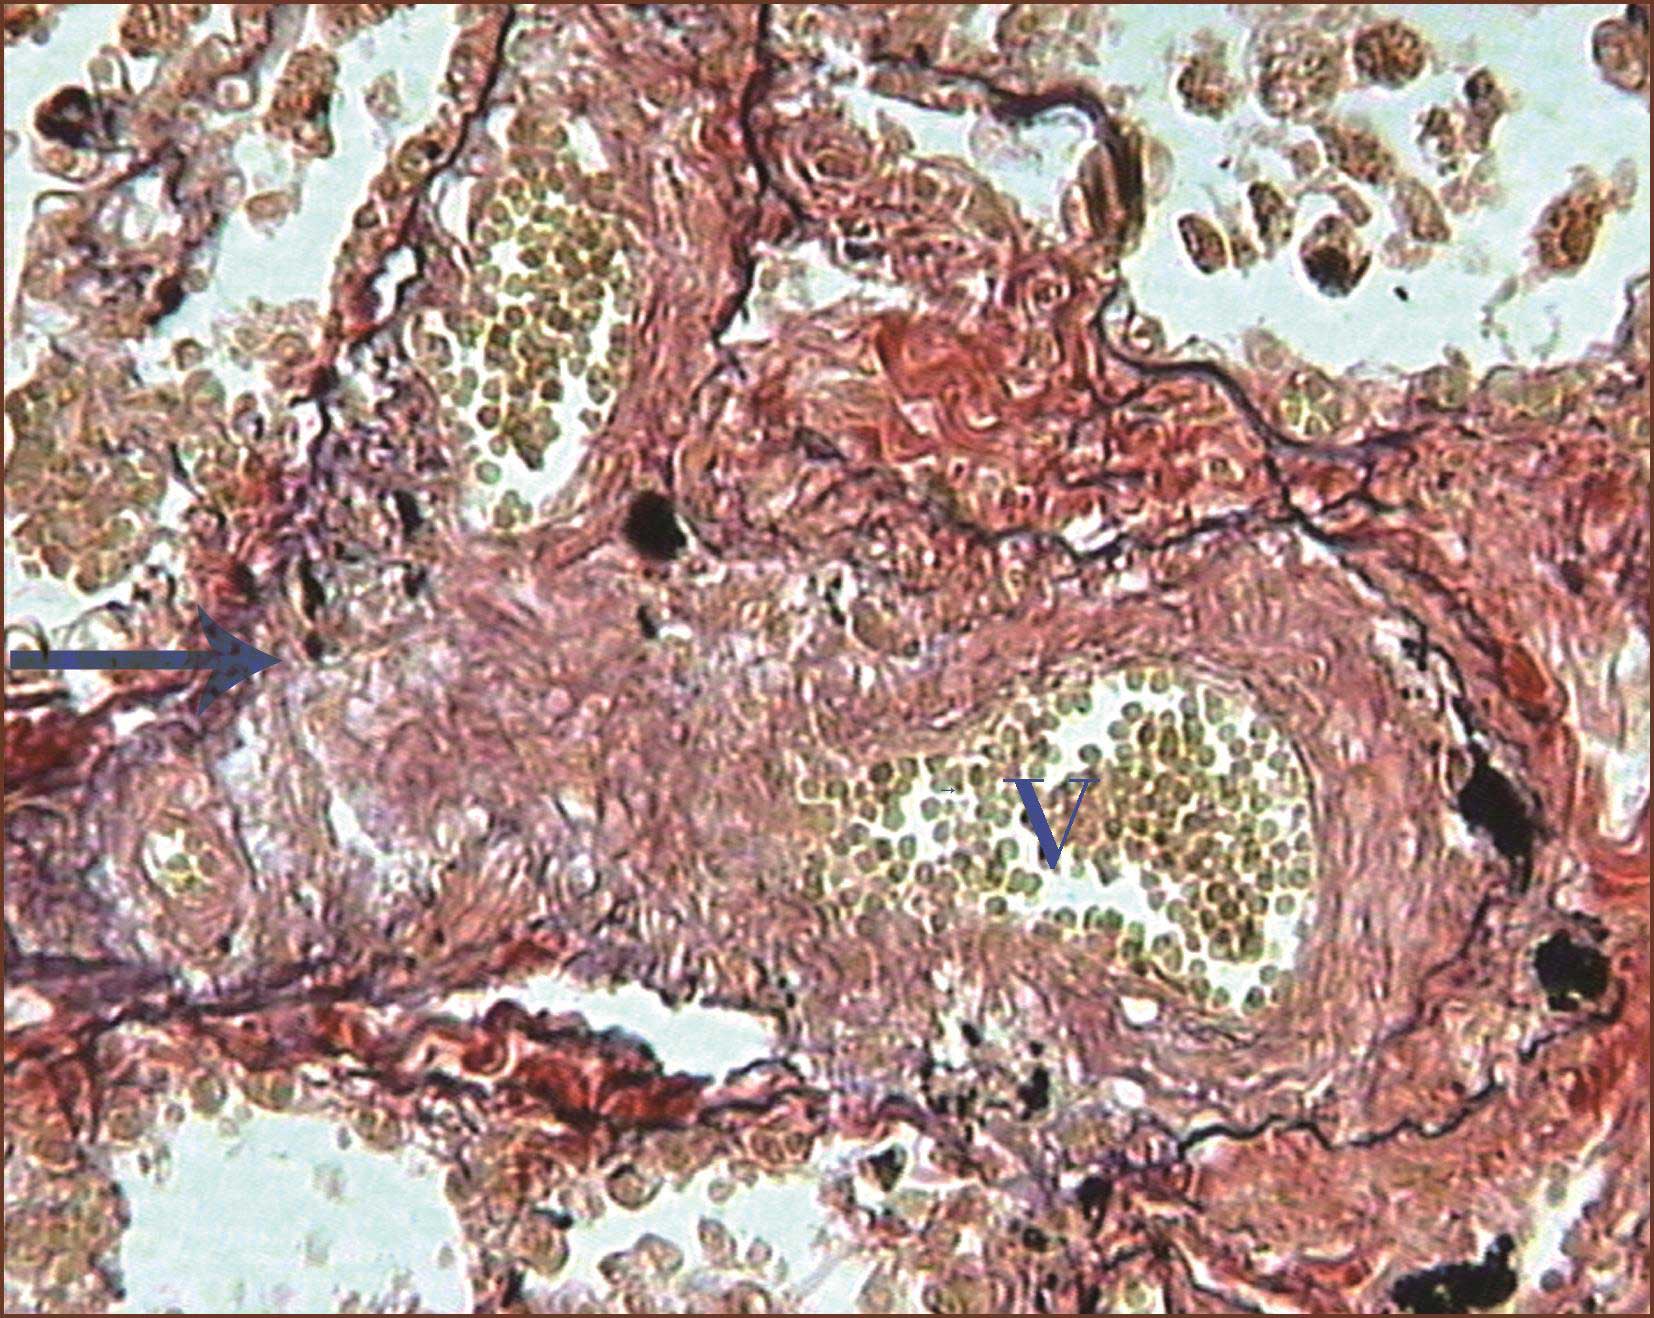

与丛状病变相关的后续病变是丛状病变后端的动脉扩张性病变(图3-1-15,图3-1-16),即血管扩张,中膜几乎消失,有时似肺小静脉。扩张性病变的血管可以是直的、纺锤形的或者团状类似海绵状血管瘤。或者表现为局部、薄壁的球样膨出类似动脉瘤。血管扩张性病变一般认为是近端血管狭窄后的继发性扩张,是坏死性动脉炎的直接结果。偶尔,在程度较轻的PAH中缺乏丛状病变,而仅见血管扩张性病变单独存在。

图3-1-15 晚期丛状病变,图下端是小血管球状增生,图上端血管腔扩大似静脉壁,为肺小动脉丛状病变后的血管扩张性病变(Masson染色,高倍放大)

图3-1-16 来自IPAH,图右上方肺小动脉腔呈筛孔状,腔内可见注射的深色钡剂(∗),图中下部的丛状病变裂隙内血管无钡剂,其他薄壁血管为扩张的肺小动脉(HE,高倍放大)